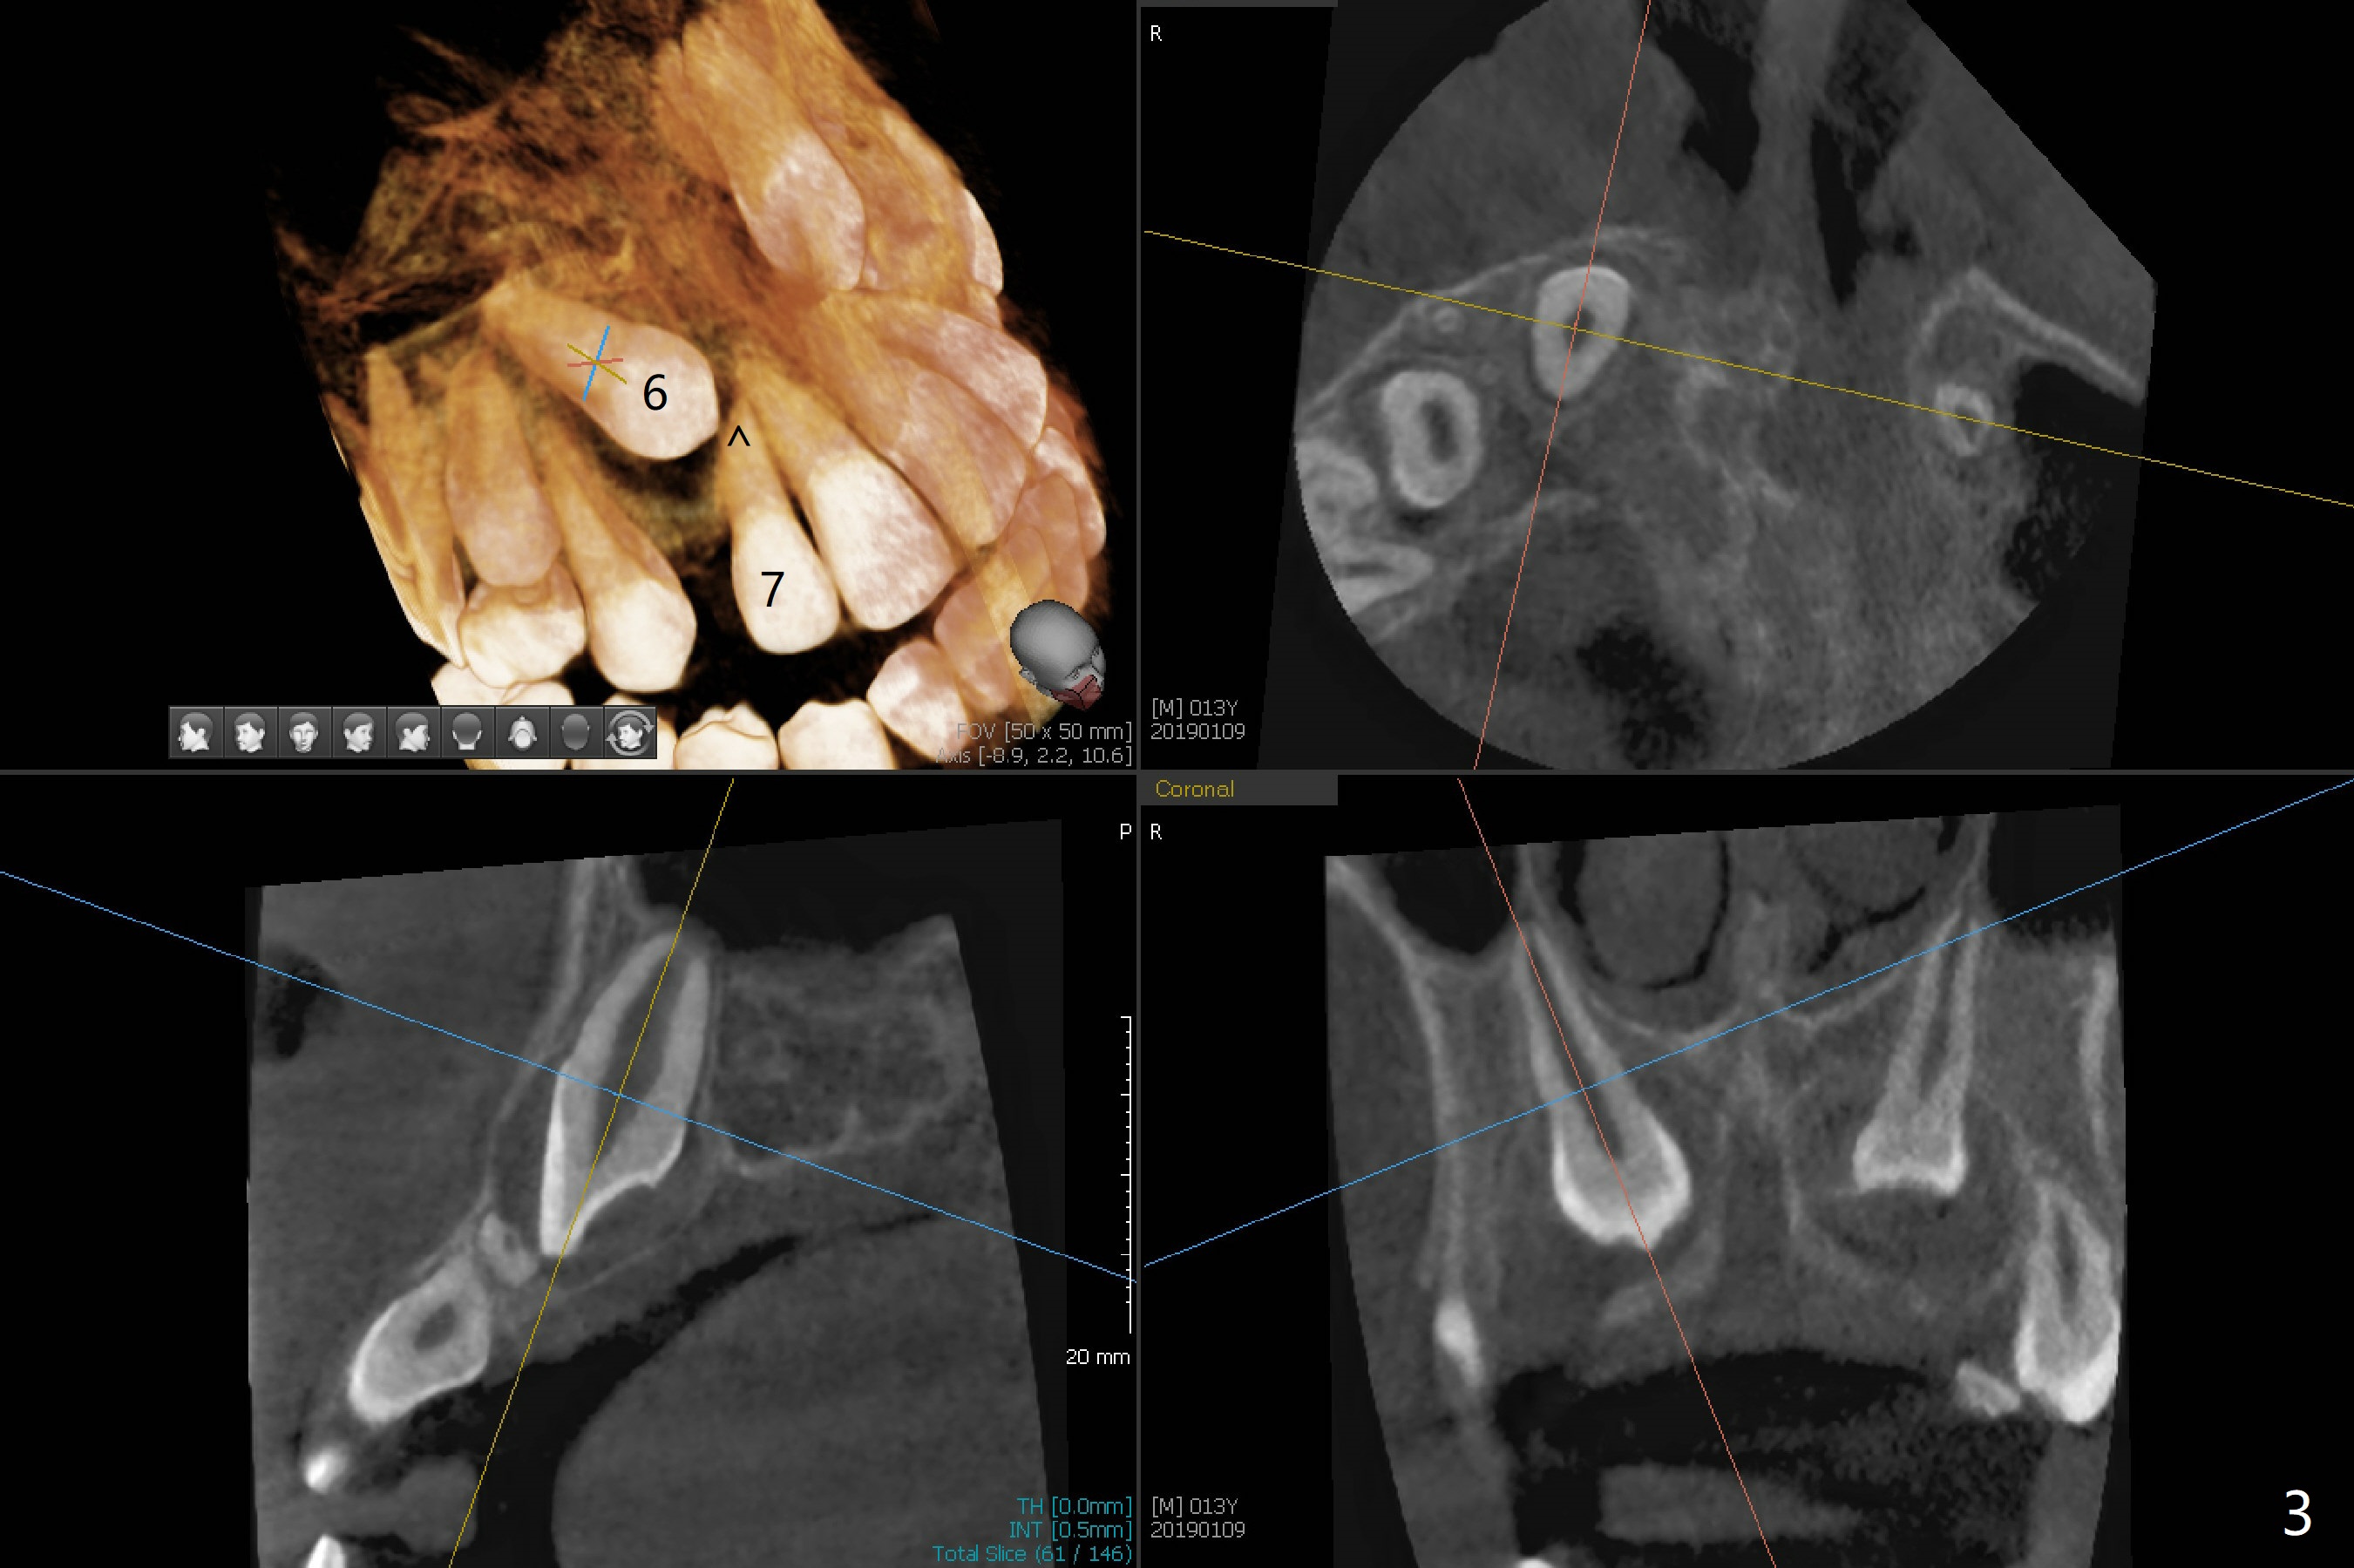

A 13-year-old boy with Class III malocclusion returns with mother from an orthodontic office for extraction of the tooth H with panoramic X-ray taken last year (Fig.1). An interesting finding was present, but not diagnosed a year earlier (Fig.2).

A cystic lesion around each of the impacted permanent upper canines. A normal dental sac or dentigerous cyst?

Discussion over Weichat indicates that there is no need to differentiate them. Both need retraction. Everything will be alright.